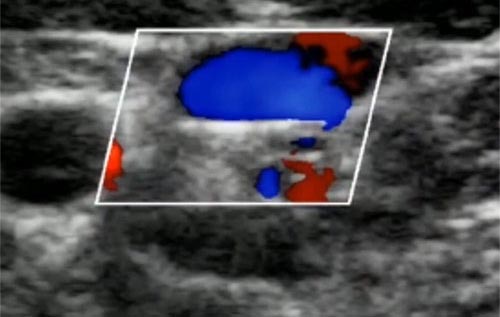

Como diferenciar veia de artéria pela imagem acima?